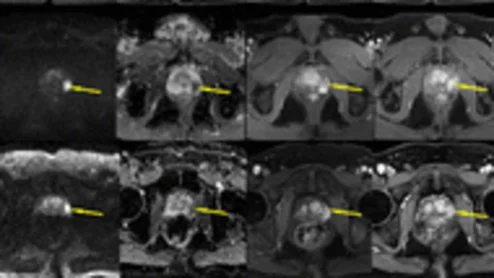

Philips UroNav system gains FDA clearance

The fusion technology integrates pre-procedural MR images of the prostate with intraprocedural ultrasound images in real-time.